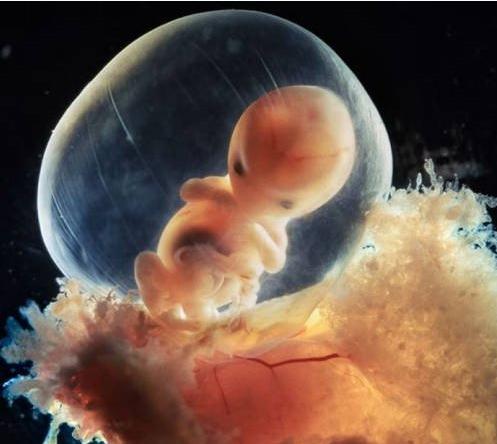

B超是产前检查的一个项目,一般来说怀孕5周就开始做B超。通过B超可以观察妊娠部位是否正常【排除宫外孕)、胚胎是否存活等。

在怀孕第13周后,B超可以清晰显现胎儿的头颅、躯干、心、肺、肝、脾、胃、肾、膀肤等器官和四肢骨骼的情况。通过测量所得的数据,可估计胎儿发育情况,还能确定胎位及胎盘位置,评价胎盘功能,选择分娩方式。

B超可以帮助释疑。如作为怀孕早期阴道流血者,B超可以确定胚胎是否存活,能否继续妊娠。B超可以确定前置胎盘及前置类型,或者是否存在胎盘早期剥离的现象;对于子宫异常增大的情况,B超可以确定是羊水过多还是多胎妊娠,还能观察胎儿有无畸形;若怀疑胎儿有染色体异常的遗传病,可在B超下抽取少量绒毛组织(宫内脐血或羊水),再进一步地做遗传检查。B超还能观察胎儿性别。